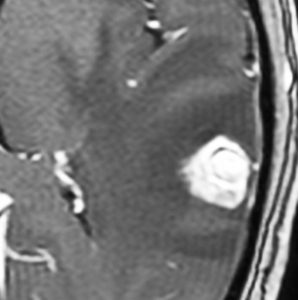

放射線治療後の再燃や脳壊死に対する脳外科手術

左側頭葉への腎癌の単発転移です。症候性てんかん(失語症発作)で発見され,定位放射線治療を受けたのですが,数ヶ月後に脳浮腫が高度となり失語症が悪化しました。コアになっている円形の転移腫瘍の周囲に放射線による脳壊死を疑いました。2時間ほどの開頭手術で,右側のガドリニウム増強されているところだけを摘出しました。

腫瘍中心の壊死の部分です。腫瘍細胞が死滅して凝固壊死の像です。血管はヒアリン化して閉塞しています。

腫瘍の辺縁部で手術中に血管が発達して出血があった部分です。腫瘍細胞 clear cell carcinoma が新生血管周囲に増殖しています。真ん中はPAS染色,右側はMIB-1染色で13%くらいの高い陽性率です。これは定位放射線治療で腫瘍が全部死滅していなくて一部では再発していることを示します。

さらに周辺と正常脳との境界部位です。脳組織が壊死になっていてます。放射線脳壊死が周囲にあって,高度の脳浮腫を生じていたことがわかりました。

この例は,定位放射線治療後に,1) ガン組織が壊死になって放射線治療の効果が認められる,2) ガン転移の再発がある,3) 放射線脳壊死が起こっている,という3つの事象が混じって生じているものです。ですから,PETやMRSなどで手術の前の画像診断を頑張ってみても,診断がつくはずがないのです。病理診断しか手段がありません。

手術1年半後の画像です。症状はなくて元気にお暮らしでした。新たな脳転移はありません。

この患者さんは幸運な方といえます。ガンを見る内科の先生に知っていただきたいのですが,今でも脳神経外科の手術は転移性脳腫瘍の治療に役に立つことがあります。